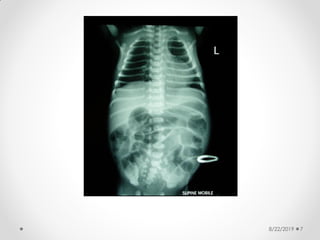

8/22/2019 7

Pneumatosis intestinalis

8/22/2019 28

8/22/2019 29

Abdominal X-ray

findings:

• Dilated bowel loops

• Thickened bowel wall

• Fixed dilated loop

• Scarce or absent intestinal gas

• Pneumatosis intestinalis:

• radiologic sign pathognomonic of NEC

• appears as a characteristic train-track

lucency configuration within the bowel wall